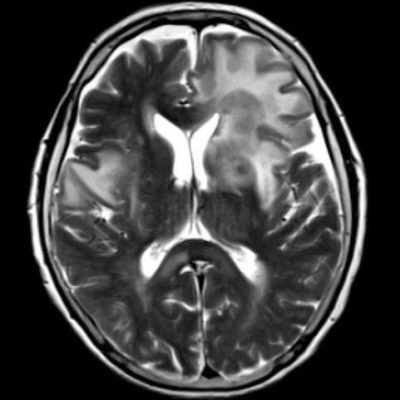

- (A) Her iki periventriküler beyaz cevherde aksiyel T2A, FLAIR serilerde hiperintens, T1A hipointens geniş ödem alanları (oklar) izlenmektedir. Sol frontalde T2A’da hipointens kitle lezyonuna (ok) dikkat ediniz.

- Genellikle supratentoriyal alanda, bazal ganglion, periventriküler beyaz cevher, orta hat ve korpus kallozum vb. yerleşme eğiliminde tek veya multipl kitleler şeklinde görülür.

- Kitleler çoğunlukla solid ve homojendir.

- MRG’de, lenfomalar tipik olarak T2A sekanslarda hipointens olup DAG’de belirgin difüzyon kısıtlanması gösterirler.